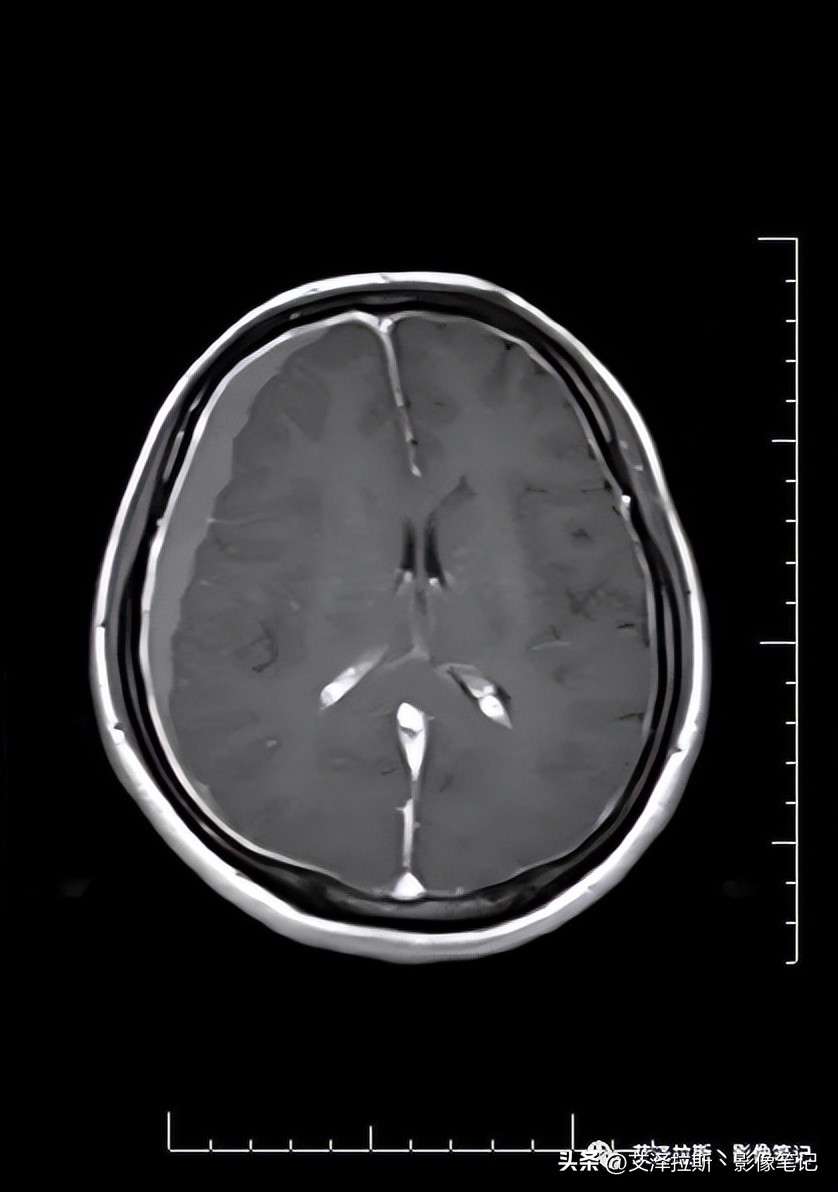

图3 T1WI

图1-4显示右侧硬膜下血肿(亚急性-慢性期)、大脑镰硬膜下血肿(亚急性期),小脑幕硬膜下血肿(未提供图片);图7-9显示硬脑膜增厚,明显均一强化,未见结节状强化,柔脑膜未见强化。

- 低颅压综合征;

- 右侧硬膜下血肿(亚急性-慢性期)、大脑镰硬膜下血肿、小脑幕硬膜下血肿(亚急性期)。